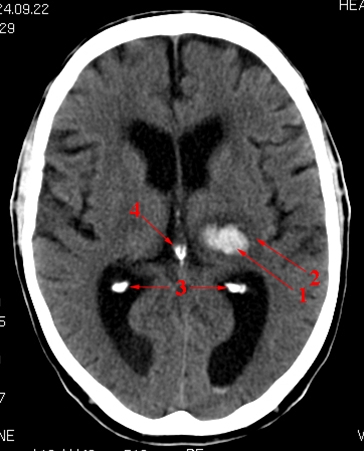

CT cerebrum uden kontrast.

Blødning (lyst område) i thalamusregionen på patientens venstre side.

Desuden ses forkalkninger (normalt) i plexus choroideus bilateralt og i corpus pineale (intenst hvide områder).

1. Blødning i thalamus

2. Ødem

3. Forkalkninger i plexus choroideus

4. Forkalkning i corpus pineale